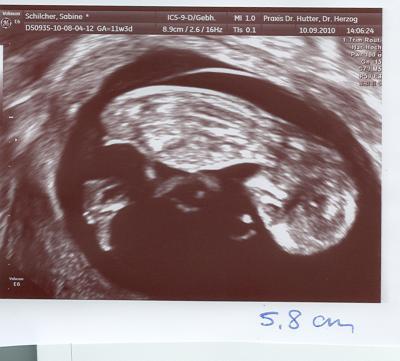

Hallo Mädels, wollte nur noch kurz berichten, dass es Baby gut geht. Es ist in einer Woche von 4,2 auf knappe 6 cm gewachsen, Herzchen hat schön geschlagen. Ich klinke mich hier erstmal aus, aber wir fahren eh erstmal nach Kroatien in den Urlaub in einer Woche. Werde mich nach meiner NFM am 27.09.10 wieder bei euch melden! Macht es gut, bis dann, Bine

Bild zu Baby gehts gut - Forum für März - Mamis

Hallo Bine, wow, was für ein geniales Foto :-)) Da kann man ja schon Geschlechterraten machen... vergleich dein Bild mal mit dieser Seite ganz unten: http://www.baby2see.com/gender/external_genitals.html Mein laienhaftes Auge würde ja jetzt sagen, das wird ein Mädchen *g* Bin gespannt, ob ich recht habe ;-)